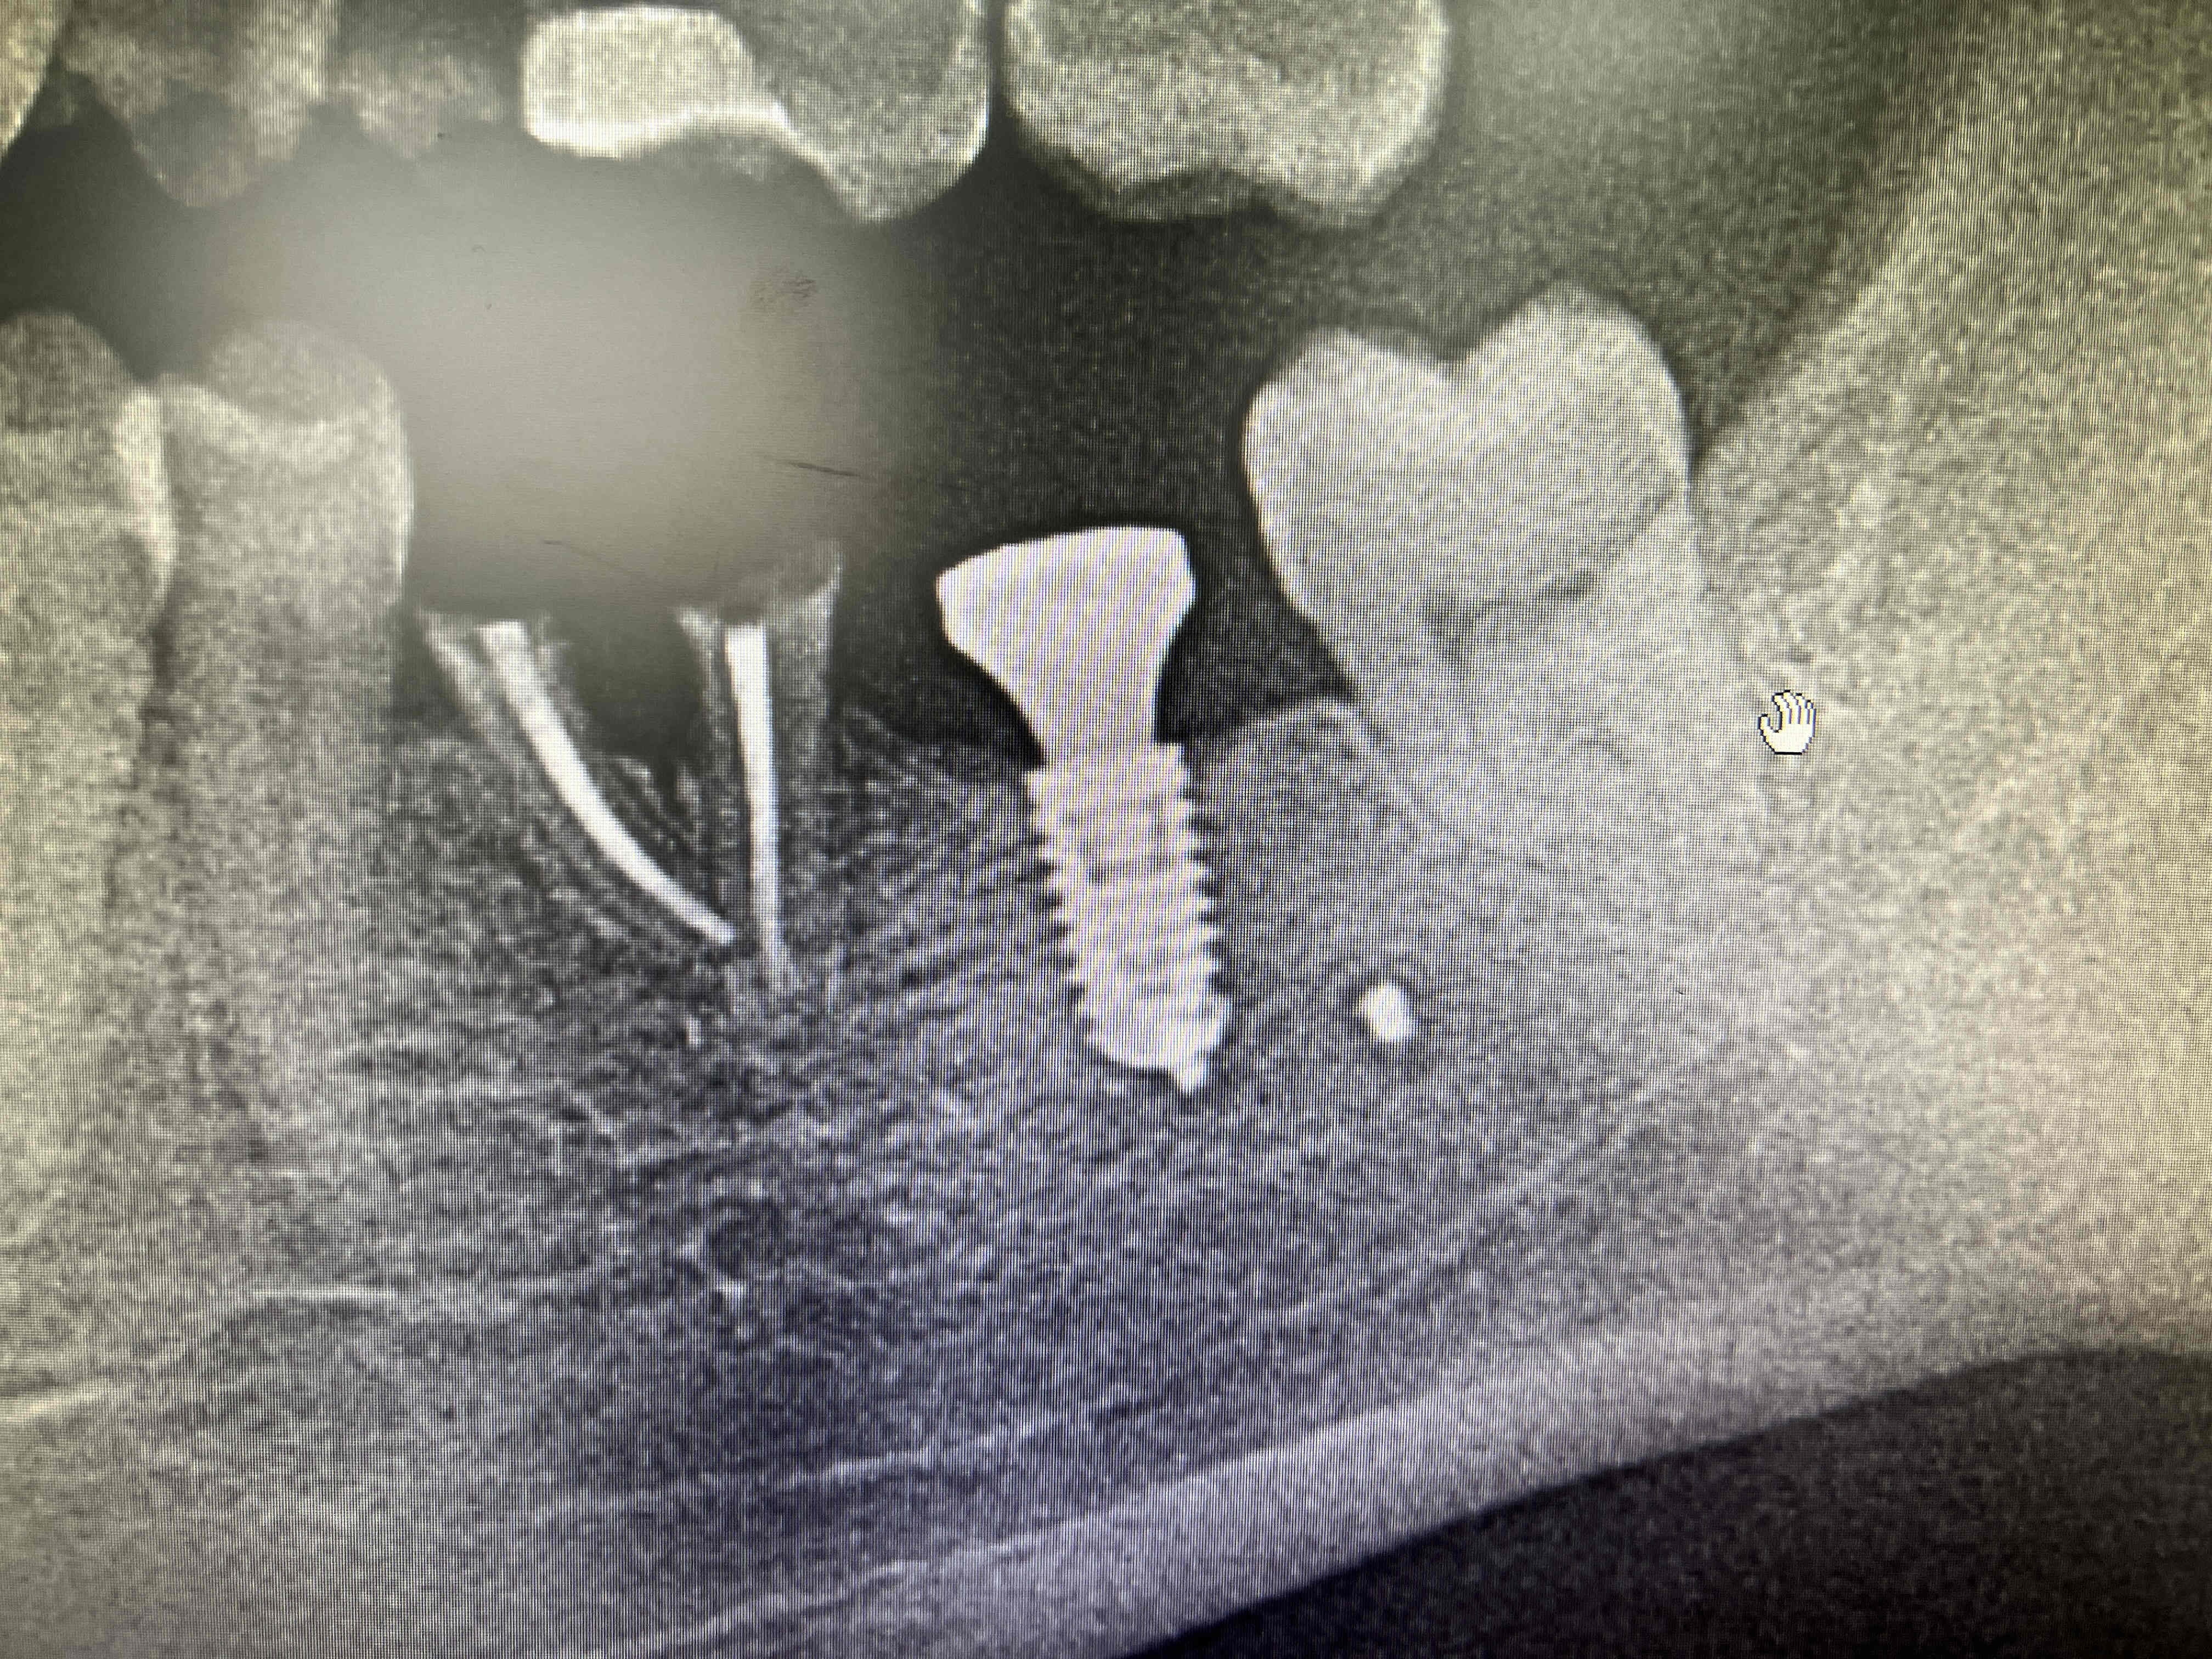

Bonjour qqn aurait il la référence de cet implant ?

Merci a vous

çà va être compliqué

Anthogyr Axiom reg

https://www.spotimplant.com/fr/implants-dentaire/anthogyr/axiom-reg